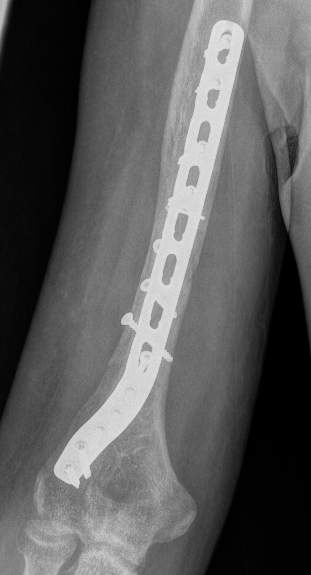

Minimally Invasive Plate Osteosynthesis (MIPO)

Concept

Bridge plating

Indirect fracture reduction

Anterior plating with narrow 4.5 mm LCP

Lateral plating with long proximal humerus plate

Jeong et al. BMC Musculoskeletal Disorders

- 18 patients treated with narrow LCP (anterior)

- 17 patients treated with long Philos plate (lateral)

- 2 metal failures in the Philos plate group requiring revision to LCP